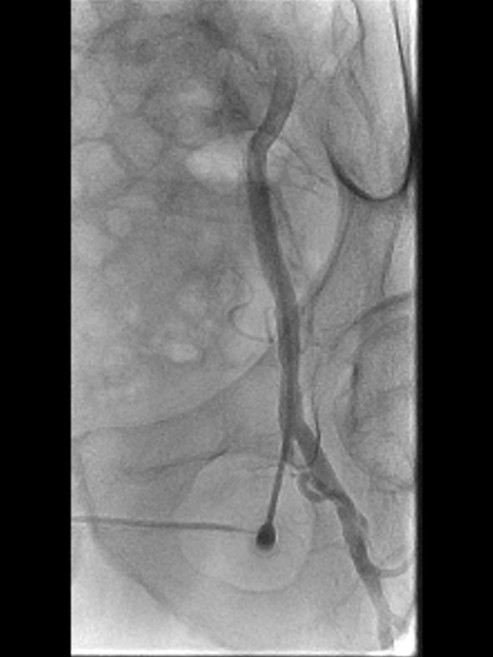

造影确认病变:长段闭塞,流出道尚可

造影显示右侧股动脉自起始段起长段闭塞,远端腘动脉及膝下动脉经股深侧枝显影,流出道条件尚可,为手术提供了基础。